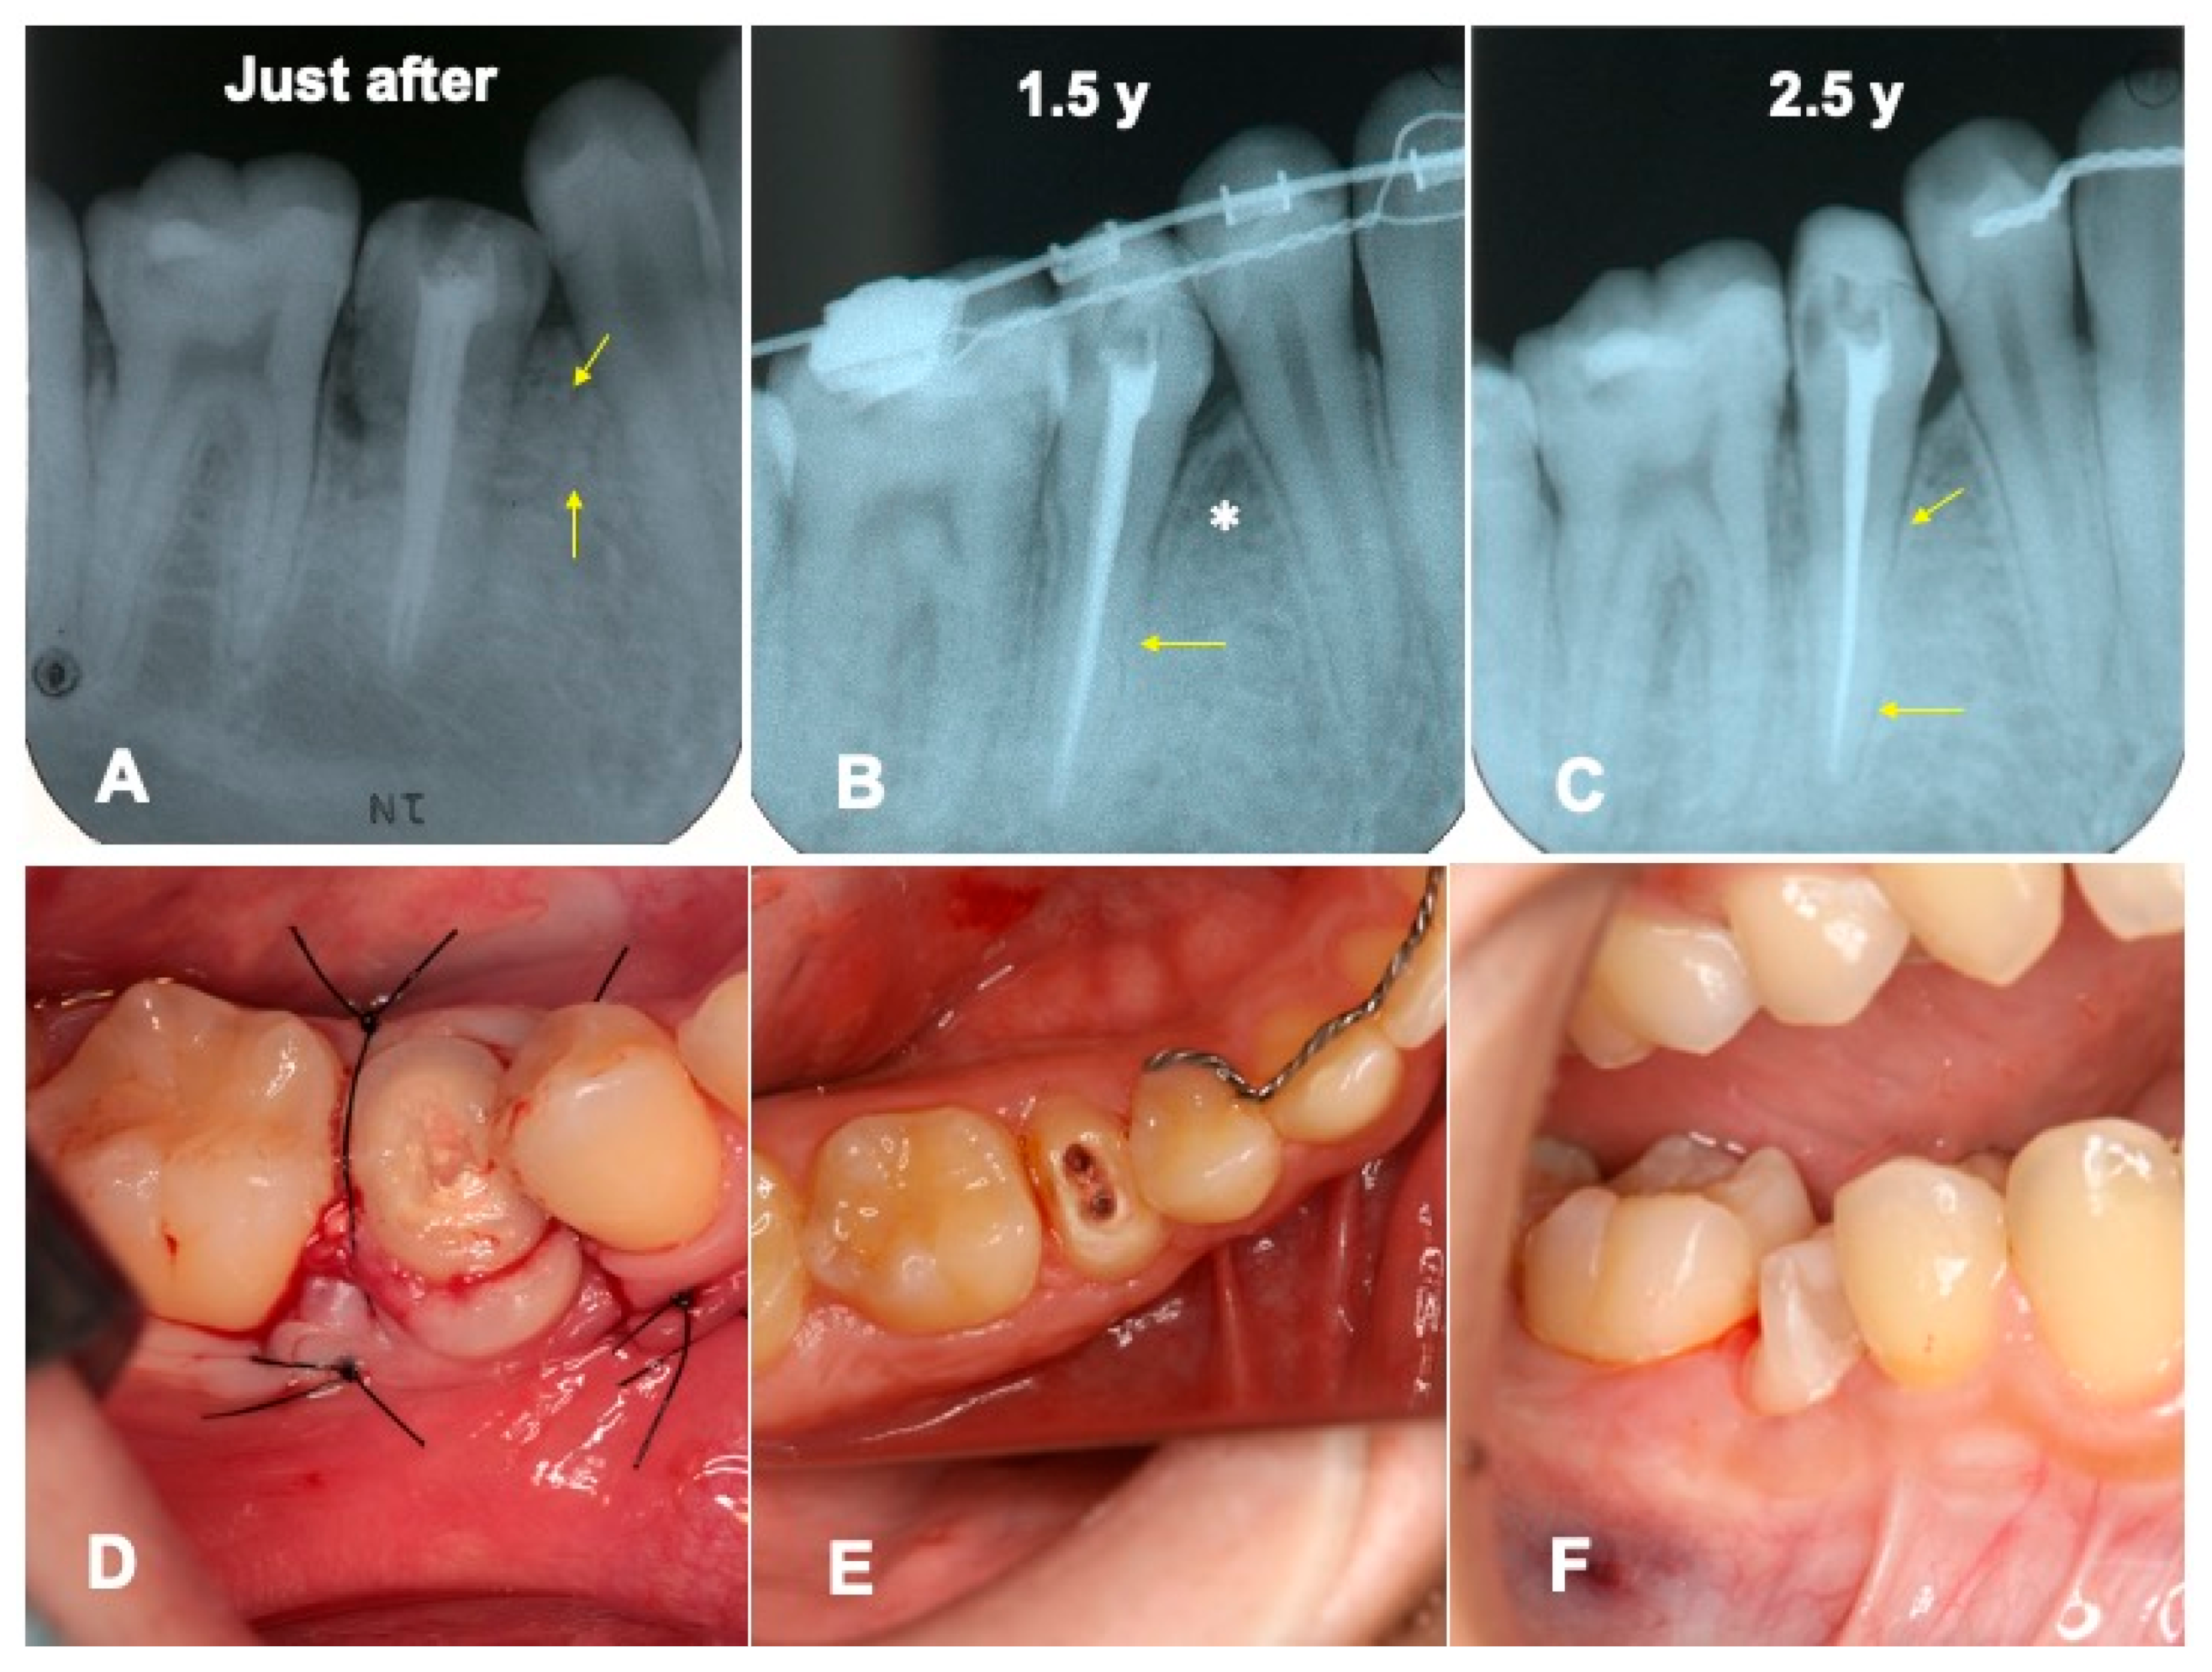

3. Results

3.1. Gross View and Examinations after Surgery

3.2. Radiographic Evaluation